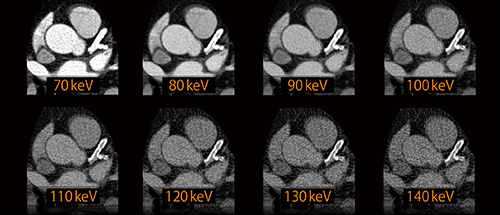

さらに,DEはステント内腔の評価や石灰化病変に対して応用されている。冠動脈のステントや石灰化領域の内腔評価は,X線CTの空間分解能の限界や拍動による動き,ステントや石灰化によるビームハードニングなどの影響のため正確な診断が困難とされている。特に,ステント内のプラーク性状評価については,ステント内腔壁の低濃度付着物を金属アーチファクトと混同しやすく,評価不能とされることも珍しくない。現在,DE Monoenergeticによる仮想単色エネルギー画像を用いることで,石灰化や金属からのアーチファクトと部分体積効果によるCT値の変動,石灰化・金属の膨張を抑えた評価が可能となっている(図2)。これにより,従来困難とされてきたステント内のプラーク性状評価について有用性が示されている5)。また,冠動脈の石灰化領域における内腔評価については,骨とヨード造影剤を識別するTwo-material decompositionアルゴリズムを用いる手法と,ヨード造影剤を抽出,定量化するThree-material decompositionアルゴリズムを用いることによって,ヨード成分から石灰化成分を分離することが可能である(図3)。いずれの手法においてもハードウェアの発展とともに着実に精度の向上を図っており,エビデンスの積み重ねと同時に,今後の冠動脈イメージングの多様化を期待させるアプローチとなっている。

図2 DE Monoenergeticによる冠動脈のステント内腔評価

金属アーチファクトと部分体積効果によるCT値の変動や,金属の膨張を抑えた冠動脈ステントの内腔評価が可能である。

(画像ご提供:アメリカ・Medical University of South Carolina様)